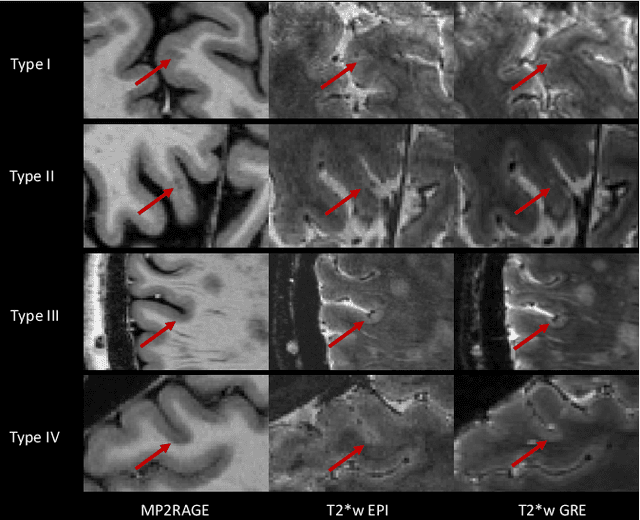

Abstract:The current multiple sclerosis (MS) diagnostic criteria lack specificity, and this may lead to misdiagnosis, which remains an issue in present-day clinical practice. In addition, conventional biomarkers only moderately correlate with MS disease progression. Recently, advanced MS lesional imaging biomarkers such as cortical lesions (CL), the central vein sign (CVS), and paramagnetic rim lesions (PRL), visible in specialized magnetic resonance imaging (MRI) sequences, have shown higher specificity in differential diagnosis. Moreover, studies have shown that CL and PRL are potential prognostic biomarkers, the former correlating with cognitive impairments and the latter with early disability progression. As machine learning-based methods have achieved extraordinary performance in the assessment of conventional imaging biomarkers, such as white matter lesion segmentation, several automated or semi-automated methods have been proposed for CL, CVS, and PRL as well. In the present review, we first introduce these advanced MS imaging biomarkers and their imaging methods. Subsequently, we describe the corresponding machine learning-based methods that were used to tackle these clinical questions, putting them into context with respect to the challenges they are still facing, including non-standardized MRI protocols, limited datasets, and moderate inter-rater variability. We conclude by presenting the current limitations that prevent their broader deployment and suggesting future research directions.

Abstract:The automated detection of cortical lesions (CLs) in patients with multiple sclerosis (MS) is a challenging task that, despite its clinical relevance, has received very little attention. Accurate detection of the small and scarce lesions requires specialized sequences and high or ultra-high field MRI. For supervised training based on multimodal structural MRI at 7T, two experts generated ground truth segmentation masks of 60 patients with 2014 CLs. We implemented a simplified 3D U-Net with three resolution levels (3D U-Net-). By increasing the complexity of the task (adding brain tissue segmentation), while randomly dropping input channels during training, we improved the performance compared to the baseline. Considering a minimum lesion size of 0.75 {\mu}L, we achieved a lesion-wise cortical lesion detection rate of 67% and a false positive rate of 42%. However, 393 (24%) of the lesions reported as false positives were post-hoc confirmed as potential or definite lesions by an expert. This indicates the potential of the proposed method to support experts in the tedious process of CL manual segmentation.